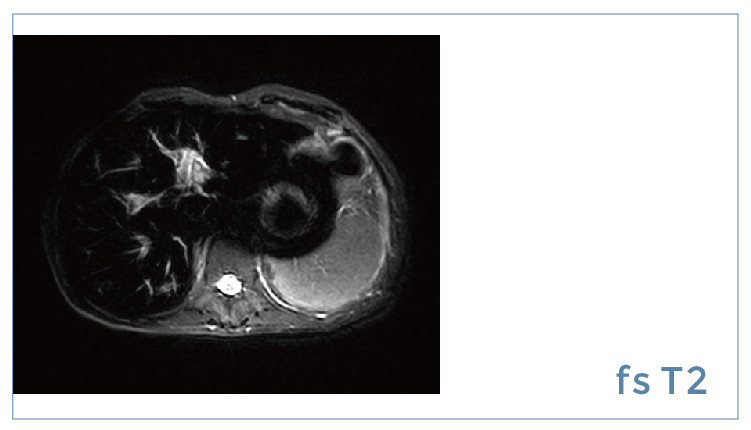

【朗润影像档案】20190906磁共振影像病例结果讨论

【朗润影像档案】磁共振影像病例分享(编号20190906)